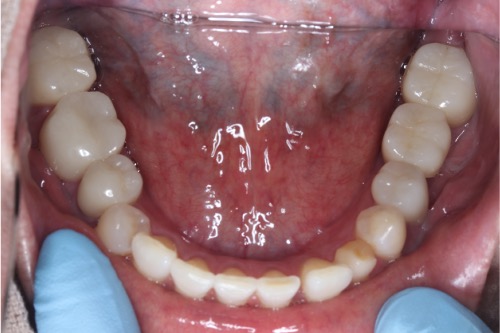

症例①

年齢40代女性

治療期間1ヶ月

治療内容セラミック治療、インプラント治療、ホワイトニング

治療箇所セラミック:左上1番、2番 左下5番、7番 右上1番、2番、3番、4番、5番 右下5番、6番、7番

インプラント:左下6番

治療費用500,000円